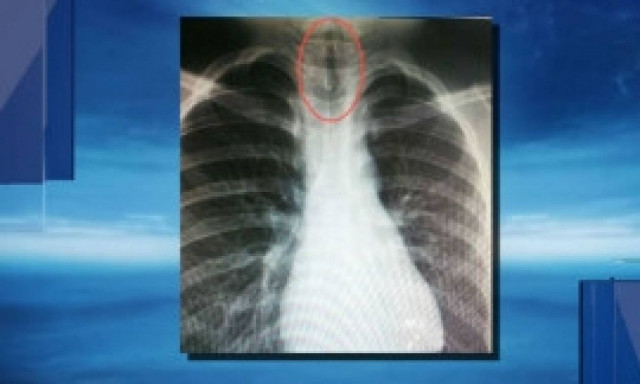

Απίστευτο: Δείτε τι βρήκαν οι γιατροί στον πνεύμονα 11χρονου αγοριού (Photos)

Μπορεί οι γιατροί να βλέπουν διάφορα περιστατικά, αλλά το συγκεκριμένο ήταν πραγματικά περίεργο...